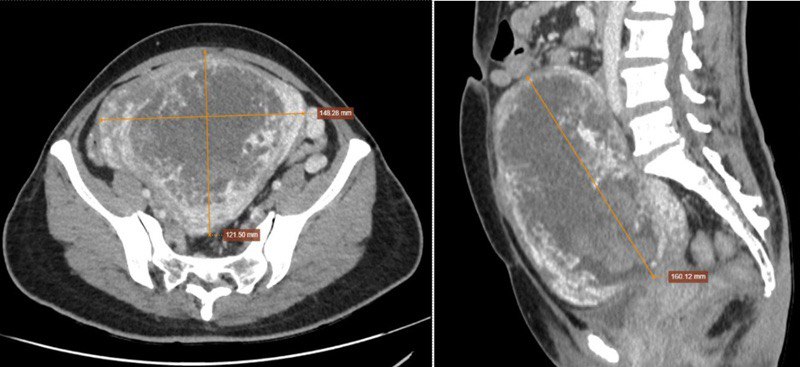

Kết quả, siêu âm cho thấy, vùng hạ vị xuất hiện khối cấu trúc hỗn hợp âm, kích thước khoảng 124 x 81mm, kèm tăng sinh mạch rõ trên siêu âm Doppler. Chụp cắt lớp vi tính (CT Scanner) ghi nhận tử cung kích thước lớn nhưng không thấy hình ảnh túi thai; bên trong là các vùng giảm tỷ trọng dạng dịch xen kẽ mô mềm, tạo hình ảnh đặc trưng dạng “bọt xà phòng”, kèm tăng sinh mạch mạnh quanh tử cung sau tiêm thuốc cản quang. Đặc biệt, nồng độ beta-hCG của bệnh nhân tăng rất cao, lên tới 2.692.965 mIU/mL.

CT Scanner thấy tử cung kích thước lớn nhưng không thấy hình ảnh túi thai (ảnh phải); bên trong có hình ảnh đặc trưng dạng “bọt xà phòng” (ảnh trái)